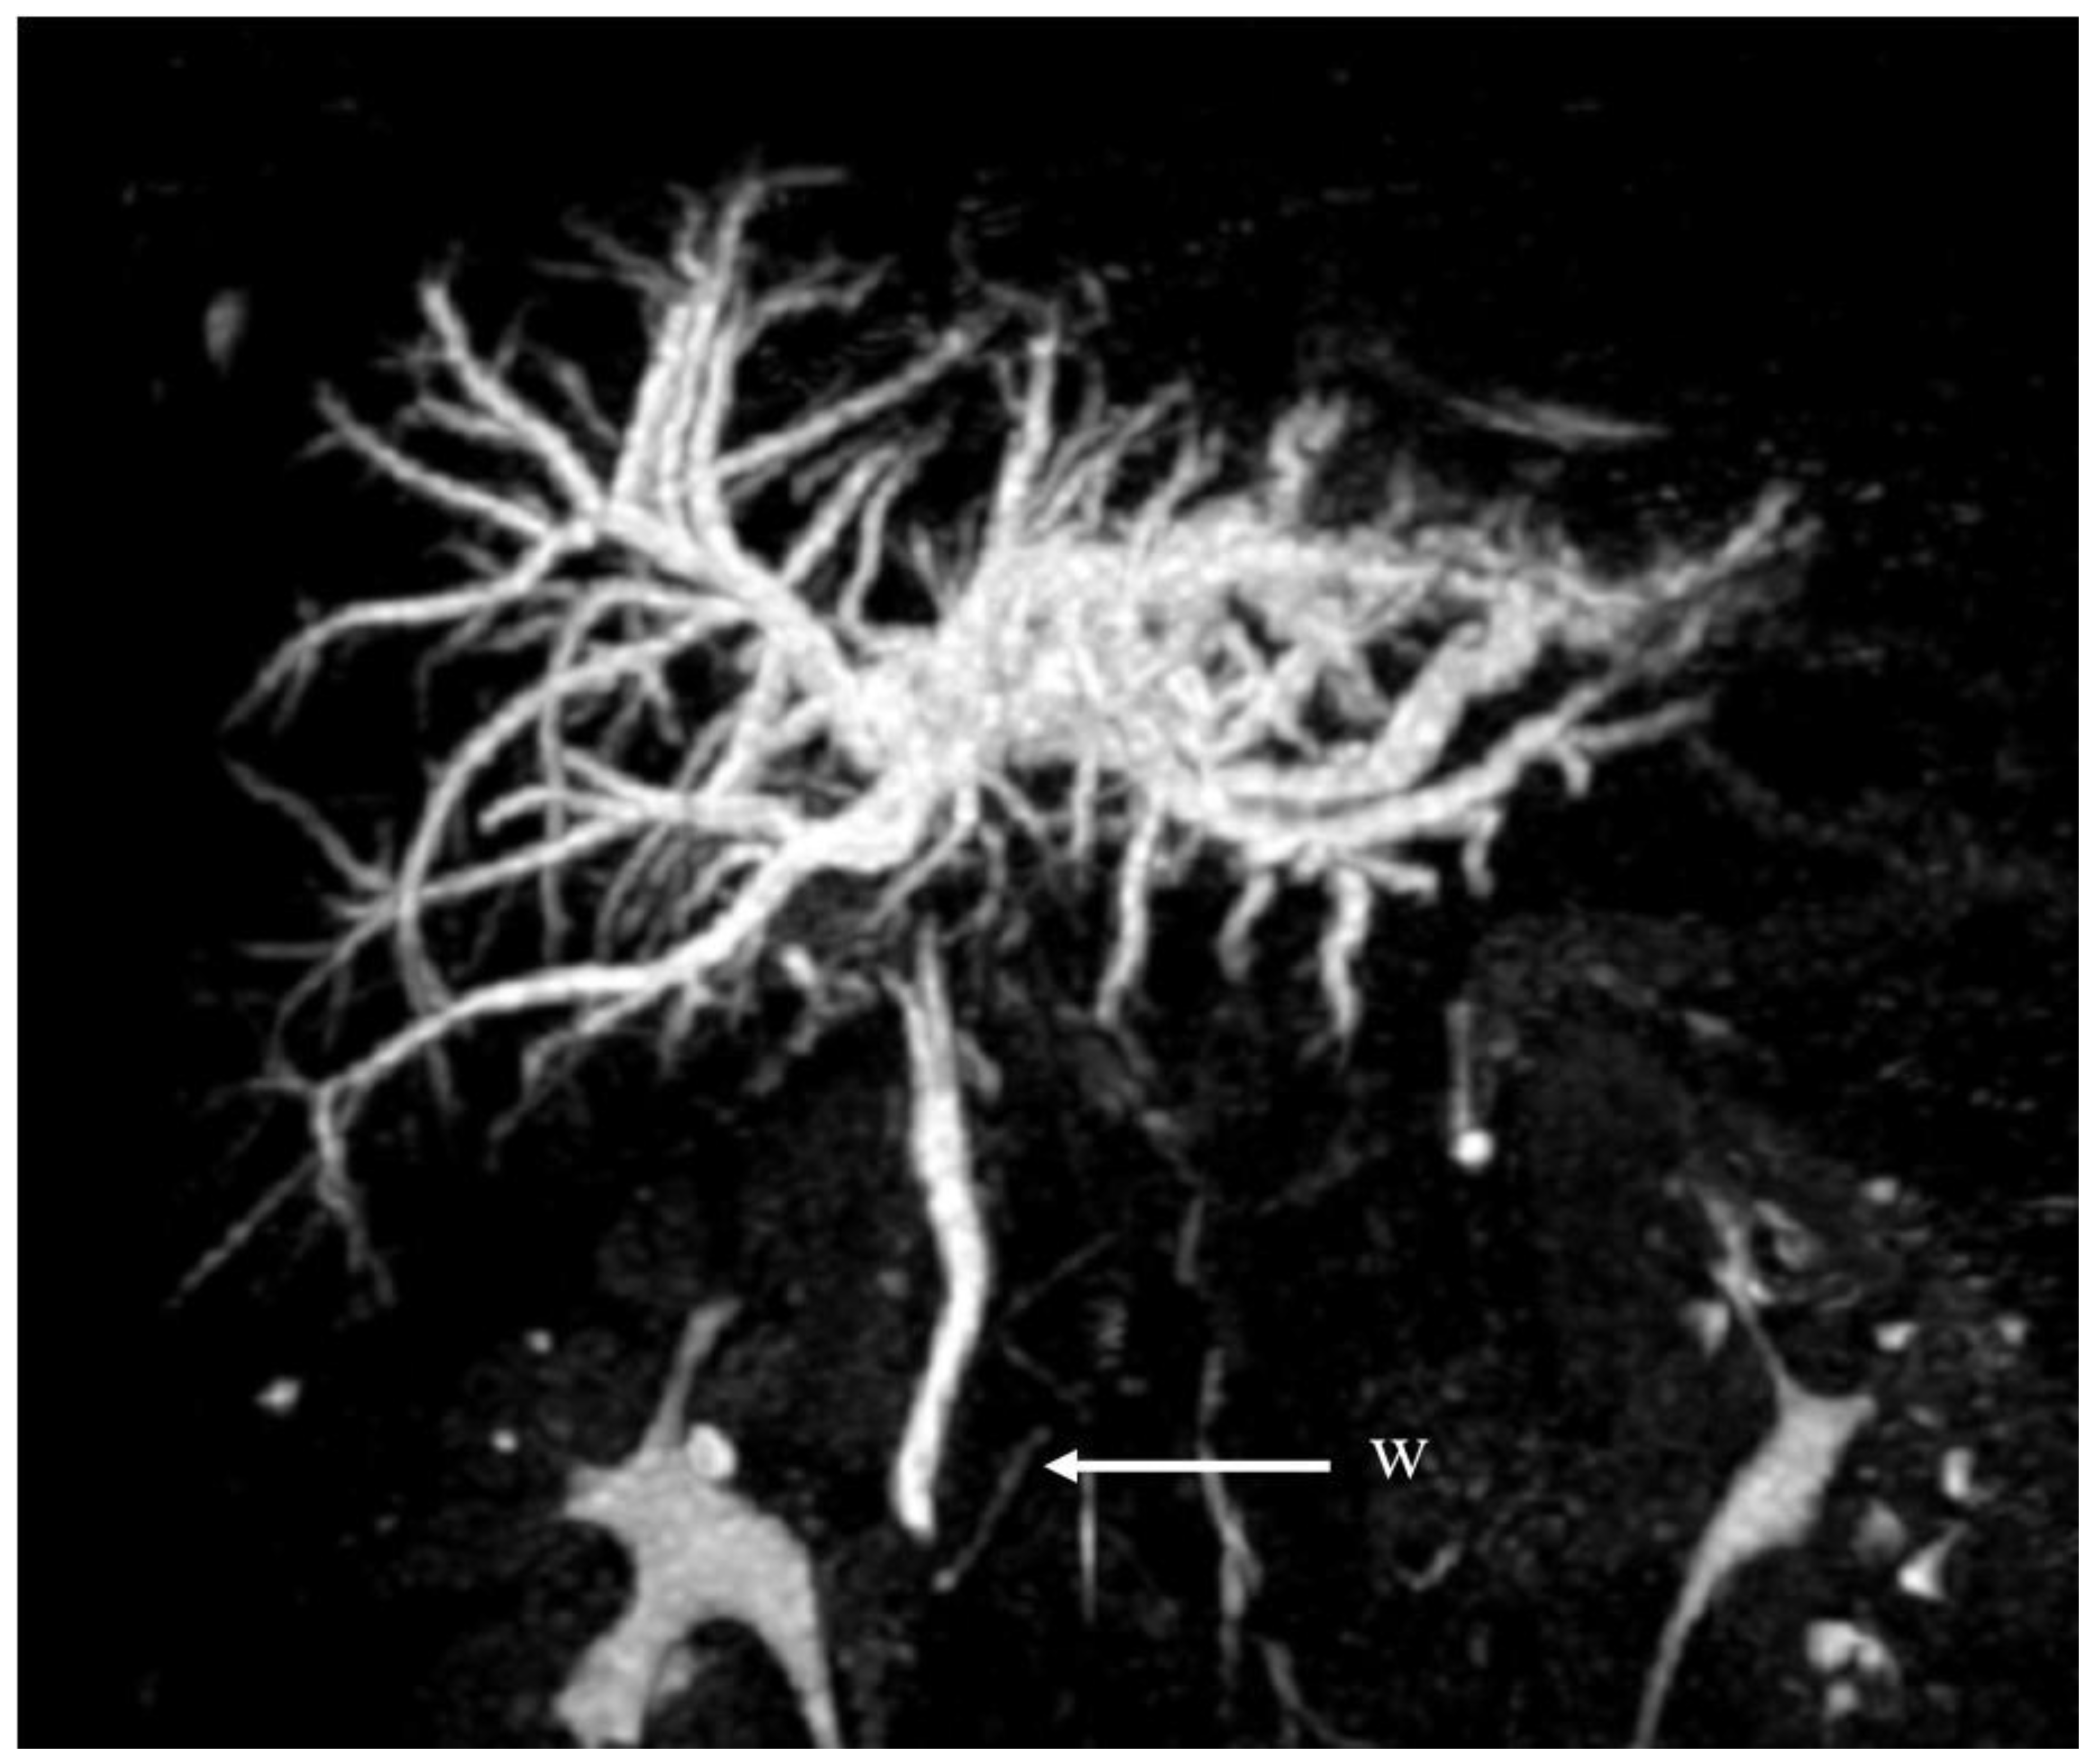

| Imaging performed | Abdominal MRI + MRCP | Abdominal CT | Abdominal CT | Abdominal MRI + MRCP | |||

| Appropriate imaging modality and features | MRCP, ERC. Beaded appearance, pruned tree appearance, and band-like stricture. | MRCP. Diffuse or segmental narrowing of the intrahepatic and/or extrahepatic bile duct, associated with the thickening of the bile duct wall. | MRCP. Intraductal calculi and bile duct strictures. | CT-scan, MRI. The CT-scan: lesions with variable c.e., may present as hypovascular with delayed enhancement because of fibrosis. The MRI may produce hypointense on T1 sequences with moderate-to-high hyperintense on T2 sequences. | CT scan (scarce sensitivity for non-calcific stones) and MRCP. | CT scan, MRCP. MRCP most accurate, shows an extrinsic narrowing of the common hepatic duct, a gallstone in the cystic duct, dilation of the intrahepatic and common hepatic ducts, with a normal common bile duct. | CT scan and portal MR and MRCP. Show portal cavernoma, paracholedochal and/or epicholedochal dilations, portosystemic shunts and abnormal morphology of the bile duct. |